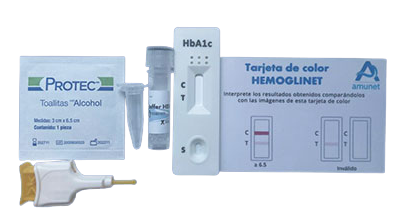

Aquí es donde Hemoglinet redefine el panorama del diagnóstico y control de la diabetes. Esta innovadora prueba de hemoglobina glicosilada (HbA1c) elimina la necesidad de equipos sofisticados y costosos.

Con solo unas gotas de sangre, Hemoglinet permite una detección cuantitativa in situ, lo que significa que el análisis puede realizarse en cualquier lugar, desde un consultorio médico hasta un entorno rural, sin la infraestructura de un laboratorio tradicional.

Si la prueba de Hemoglinet muestra dos líneas encendidas, indica que el nivel de hemoglobina glicosilada del paciente está por encima del 6.5%, un claro signo de descontrol o diagnóstico de diabetes que requiere atención inmediata.